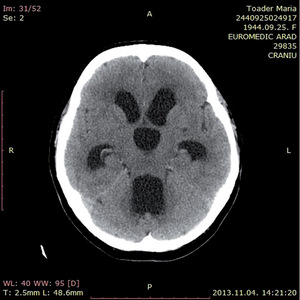

3.6.1. Hydrocephalus (59–63. ábra)

- Koponya-CT: kamrák mérete– frontalis kamraszarv/belső koponya átmérő,temporalis kamraszarvak nagysága,periventricularis liquorkilépés jele,külső liquorterek komprimáltsága.